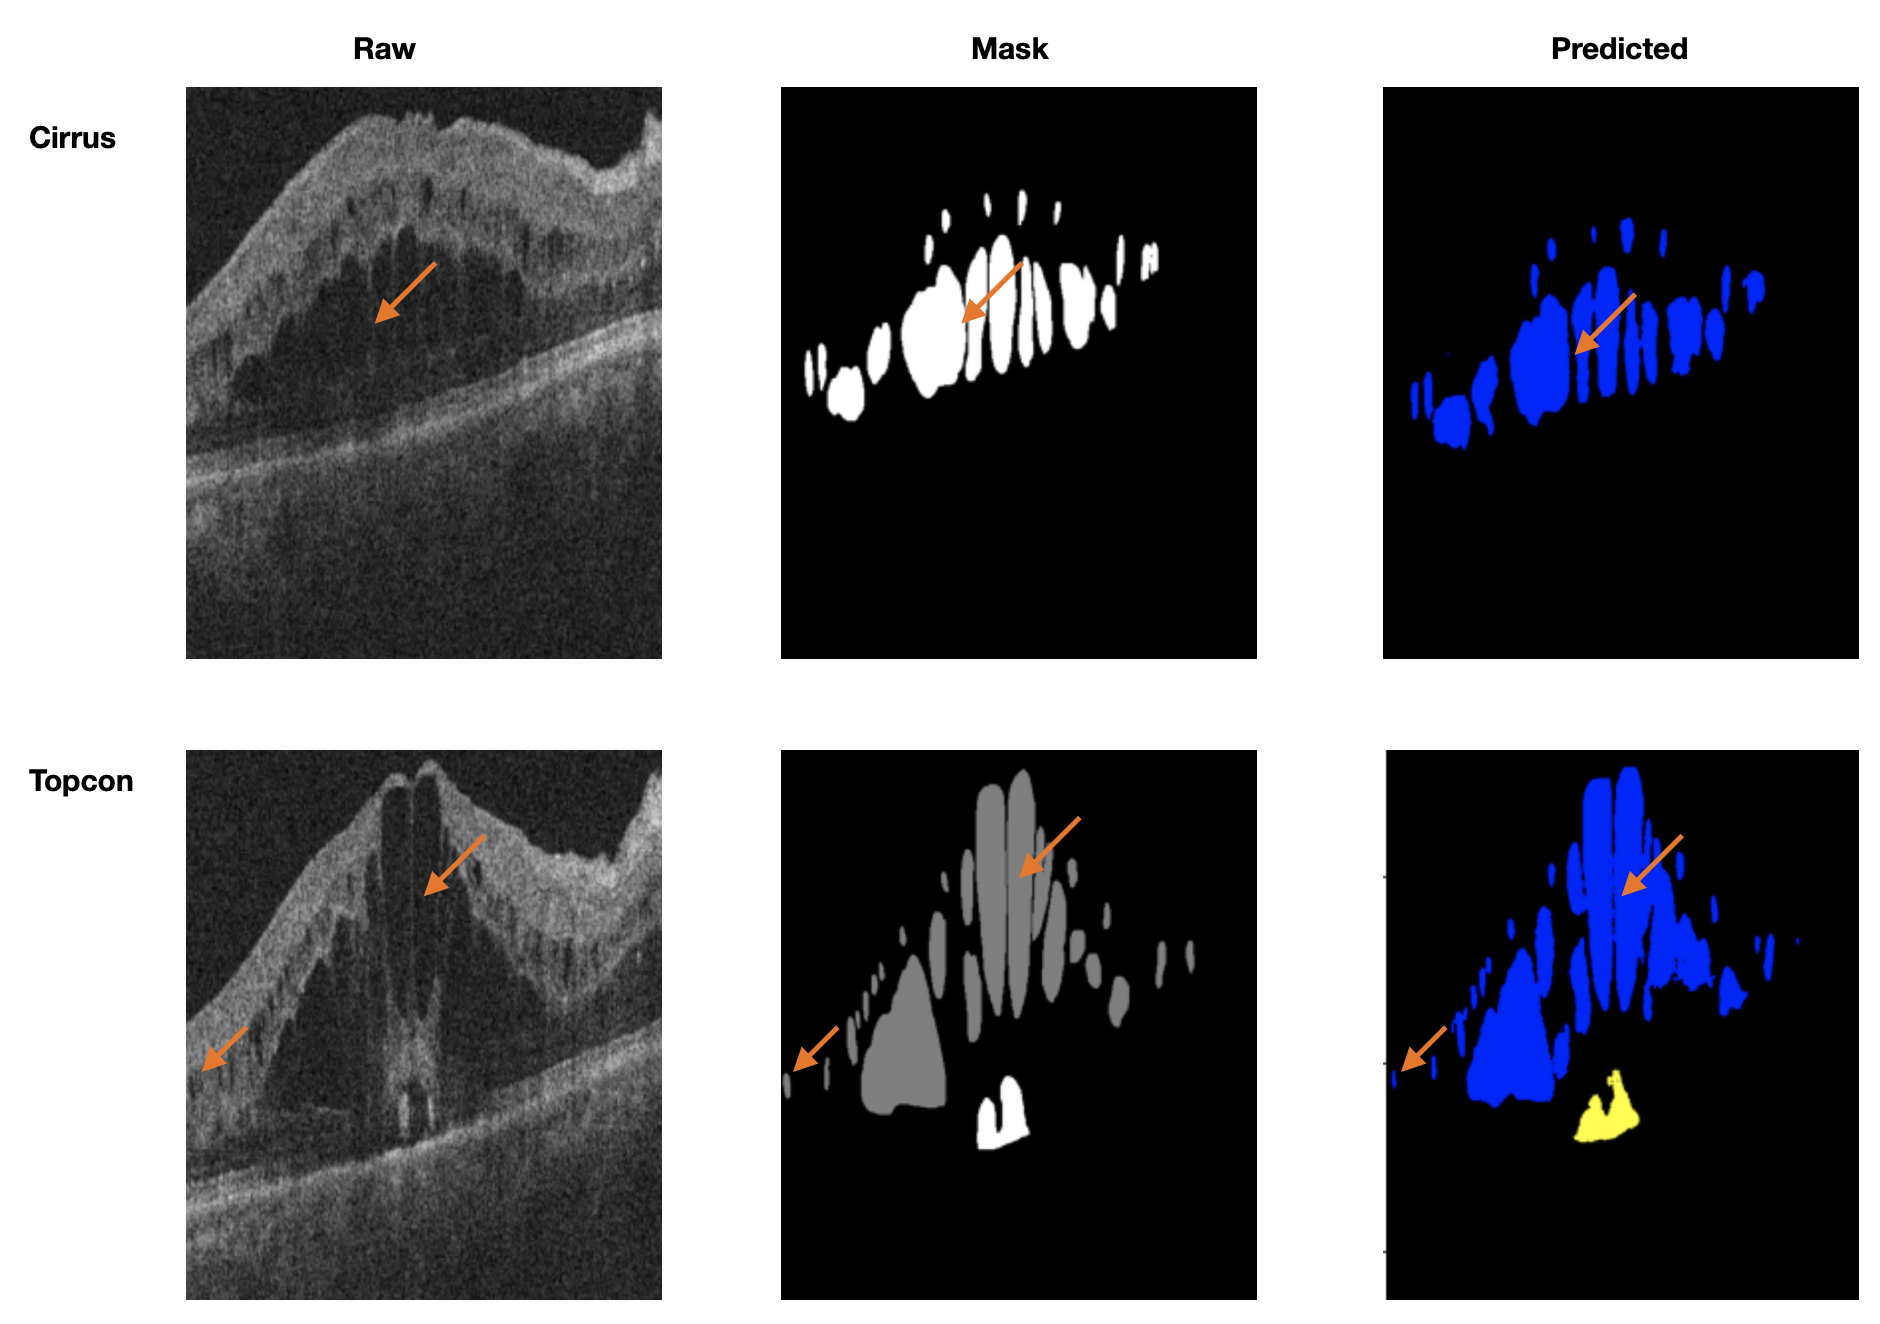

The visualizations using orange arrows to highlight the fine details capture by nnUnet_RASPP when trained on two vendor devices from the training set and tested on the third from the training set are illustrated in Fig. 13 and Fig. 14. From these results, we notice the following:

Also, to further demonstrate the robustness and generalisability of nnUnet_RASPP, the predicted segmentation of the algorithm was evaluated on OCT volumes from two vendor devices and tested on the third. In this case OCT volumes from the third vendor device weren’t seen during training. For this experiment, two sets of weights were generated which are: (1) Training on 46 OCT volumes from both Spectralis (24 OCT volumes) and Topcon (22 OCT volumes) and evaluated on 14 OCT volumes from the Cirrus testing set and (2) training on 48 OCT volumes from both Cirrus (24 OCT volumes) and Spectralis (24 OCT volumes) and evaluated on 14 OCT volumes from the Topcon testing set. Again the same environmental settings were used to conduct all the experiments.